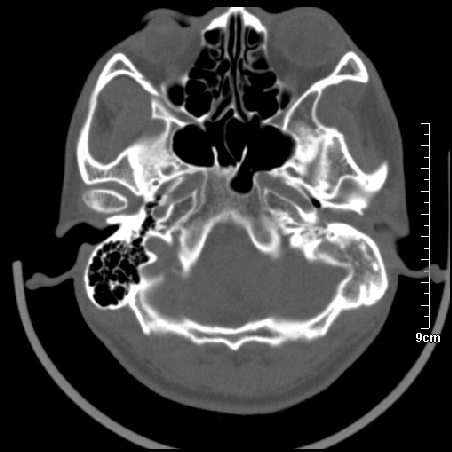

病例1

m/46y 头晕.耳鸣半月余 有乳突炎病史

胆脂瘤是是以鳞状上皮内衬充满角质化碎片的囊,随着角化屑片的不断堆积,肿块逐渐增大,胆脂瘤可为先天性(2%)或后天性(98%)。胆脂瘤有感染史。中耳内的鳞状上皮通常有外耳道的上皮通过一鼓膜的缺损移行至中耳,其他的原因包括鳞状上皮化生。由于欧氏管的功能不全所引起的中耳负压可产生上鼓室鼓膜松弛部的牵引性开袋。继而发展成胆脂瘤。成年人胆脂瘤时乳突常发育差,而儿童常有广泛性乳突气化,这种气化可导致胆脂瘤的更广泛的乳突扩散。后天性胆脂瘤患者大多数存在骨质破坏。

松弛部胆脂瘤有中央性穿孔或后上部牵引口袋所致。紧张部胆脂瘤经常侵蚀听小骨并引起传导性耳聋。

中耳胆脂瘤有两个重要并发症:一是面神经管的水平段受暴露,二是外侧半规管受侵蚀产生瘘管。面神经在ct上难以显示或不可能显示,除非其周围有空气包绕或有良好轮廓的骨性覆盖。胆脂瘤还可合并感染,产生于急性中耳炎.乳突炎所描述的那些合并症。